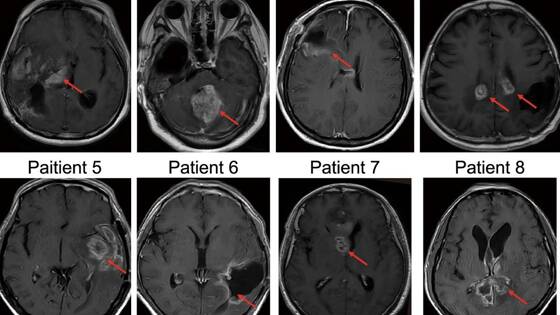

В ходе испытаний восемь пациентов с рецидивом глиобластомы, вернувшихся после операции, получили одну из трех доз вируса Ad-TD-nsIL12. Этот вирус создан на основе аденовируса, который обычно вызывает простудные заболевания, но был модифицирован для локальной доставки IL-12 — мощного иммуностимулирующего белка — непосредственно к области опухоли.

В результате удалось определить максимальную дозу, при которой лечение оставалось безопасным и хорошо переносилось пациентами. Наблюдались побочные эффекты лишь легкой или средней тяжести, что подтверждает возможность дальнейших испытаний на более широком круге пациентов. Одному пациенту удалось достичь полной ремиссии опухоли, у другого наблюдалось значительное уменьшение размеров опухоли.